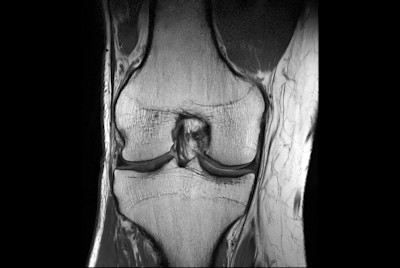

Fast Knee imaging with SmartSpeed Precise

SmartSpeed 2 min Knee imaging

SmartSpeed Traumatic Knee imaging

Knee ACL repair

Knee with lesion

Push-button Knee exam, under 5 minutes

High quality Knee imaging in short scan times

Knee imaging with Compressed SENSE

Knee exam with/without Compressed SENSE

Knee Imaging with Cartilage Assessment

Metal Imaging of the Knee

3D Knee imaging with MSK VIEW

Knee imaging

Comprehensive 3D knee imaging with MSK VIEW